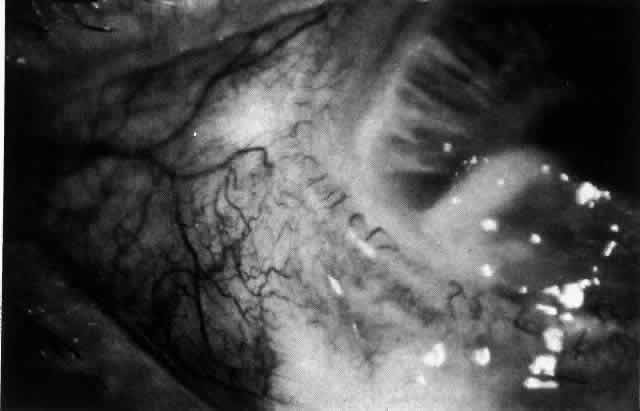

The characteristic features of necrotizing scleritis on fluorescein angiography are hypoperfusion and, eventually, nonperfusion of the vascular networks (Figs. 40 through 43).26 The initial changes are on the venous side of the capillary network; the transit time of the dye increases even if the eye is red and congested. If the disease process persists or has been present for a long time, thrombosis and permanent vaso-occlusive changes occur. These vessels (or the occluded capillary network) are bypassed by the opening of anastomotic channels. New vessels in a granuloma give rise to deep intrascleral leakage of dye (see Fig. 43). Conjunctival and episcleral involvement by the destructive change is late but is always preceded by vaso-occlusive changes that can sometimes be detected with use of the red-free light on the slit lamp (Figs. 44 and 45).

Fig. 44. Necrotizing scleritis. An avascular patch is seen in red-free light. If left untreated, this will progress to the situation found in Figure 45.

Fig. 45. Necrotizing scleritis. An area of necrosis is evident in the eye of this patient with localized Wegener's granulomatosis. The conjunctiva adjacent to the white necrotic tissue becomes adherent to the underlying episclera.